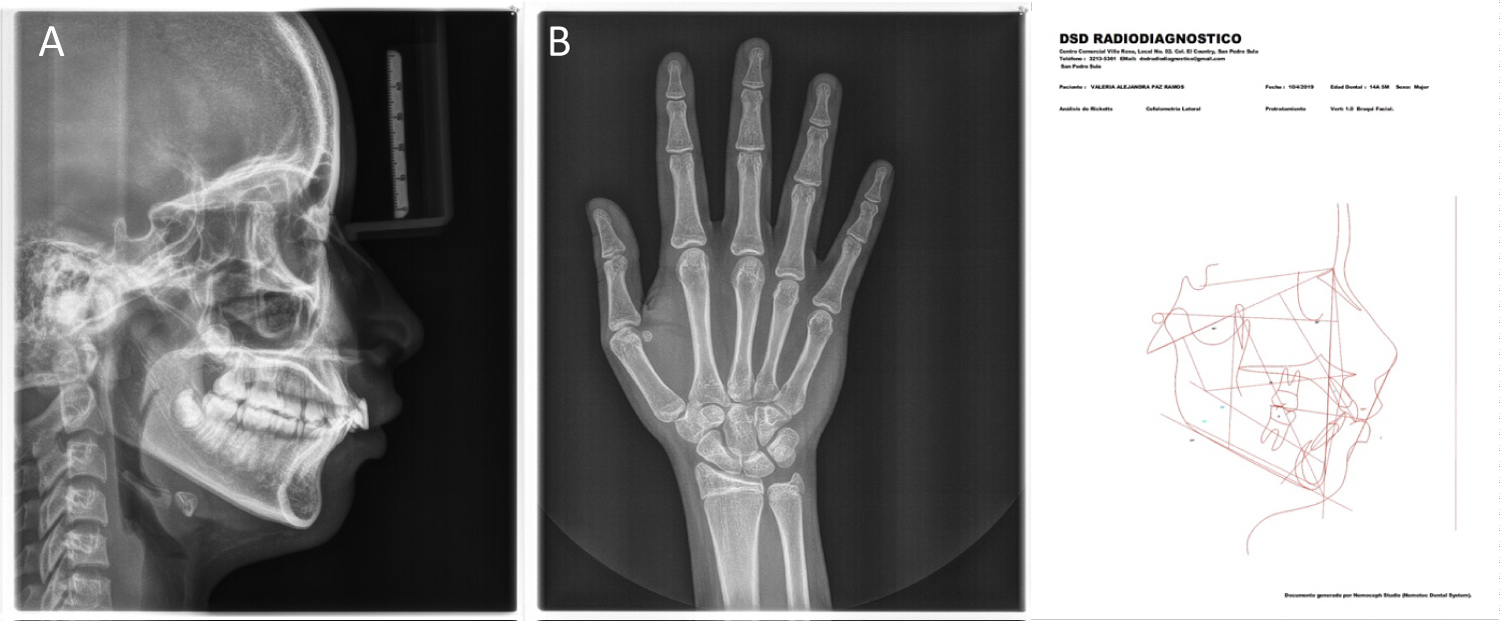

Additionally, cephalometric analysis and hand/wrist radiographs were analyzed to identify the physical development stage of the patient and correlate them to the chronological age. (Once skeletal maturity was assessed and appropriate surgical and prosthetic treatment plan was outlined, surgical procedure could be performed) (Figure 3).

Figure 3: (A) Lateral radiograph; (B) Hand and wrist radiography; (C) Cephalometric analysis. View Figure 3

Skeletal growth status can be appraised fairly accurately by comparing a conventional radiograph of the hand and wrist against a standardized atlas of hand and wrist bone development. Hand wrist radiograph indicators can be used to place a patient in the general area of the growth curve. Capping of the middle phalanges of the third finger (MP3cap) usually occurs after maximum growth velocity is completed and indicates a deceleration in the pubertal growth spurt. Once pubertal growth is completed, consideration of implant placement can begin. However, some risks still exist. When epiphysis of the radius fuses and forms a bony union with the diaphysis, the adult level of skeletal growth has been attained and no further increase in structural height can be expected [10].